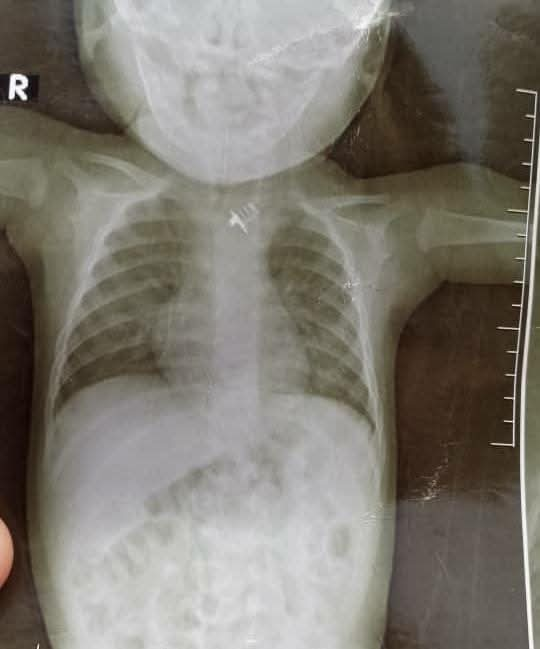

نجاح عملية نادرة في مستشفى بن زيلع الحديث لإنقاذ رضيع ابتلع قطعة حديد

تمكّن الطاقم الطبي في مستشفى بن زيلع الحديث من إنقاذ حياة طفل يبلغ من العمر 6 أشهر، ابتلع قطعة حديد من ريموت،